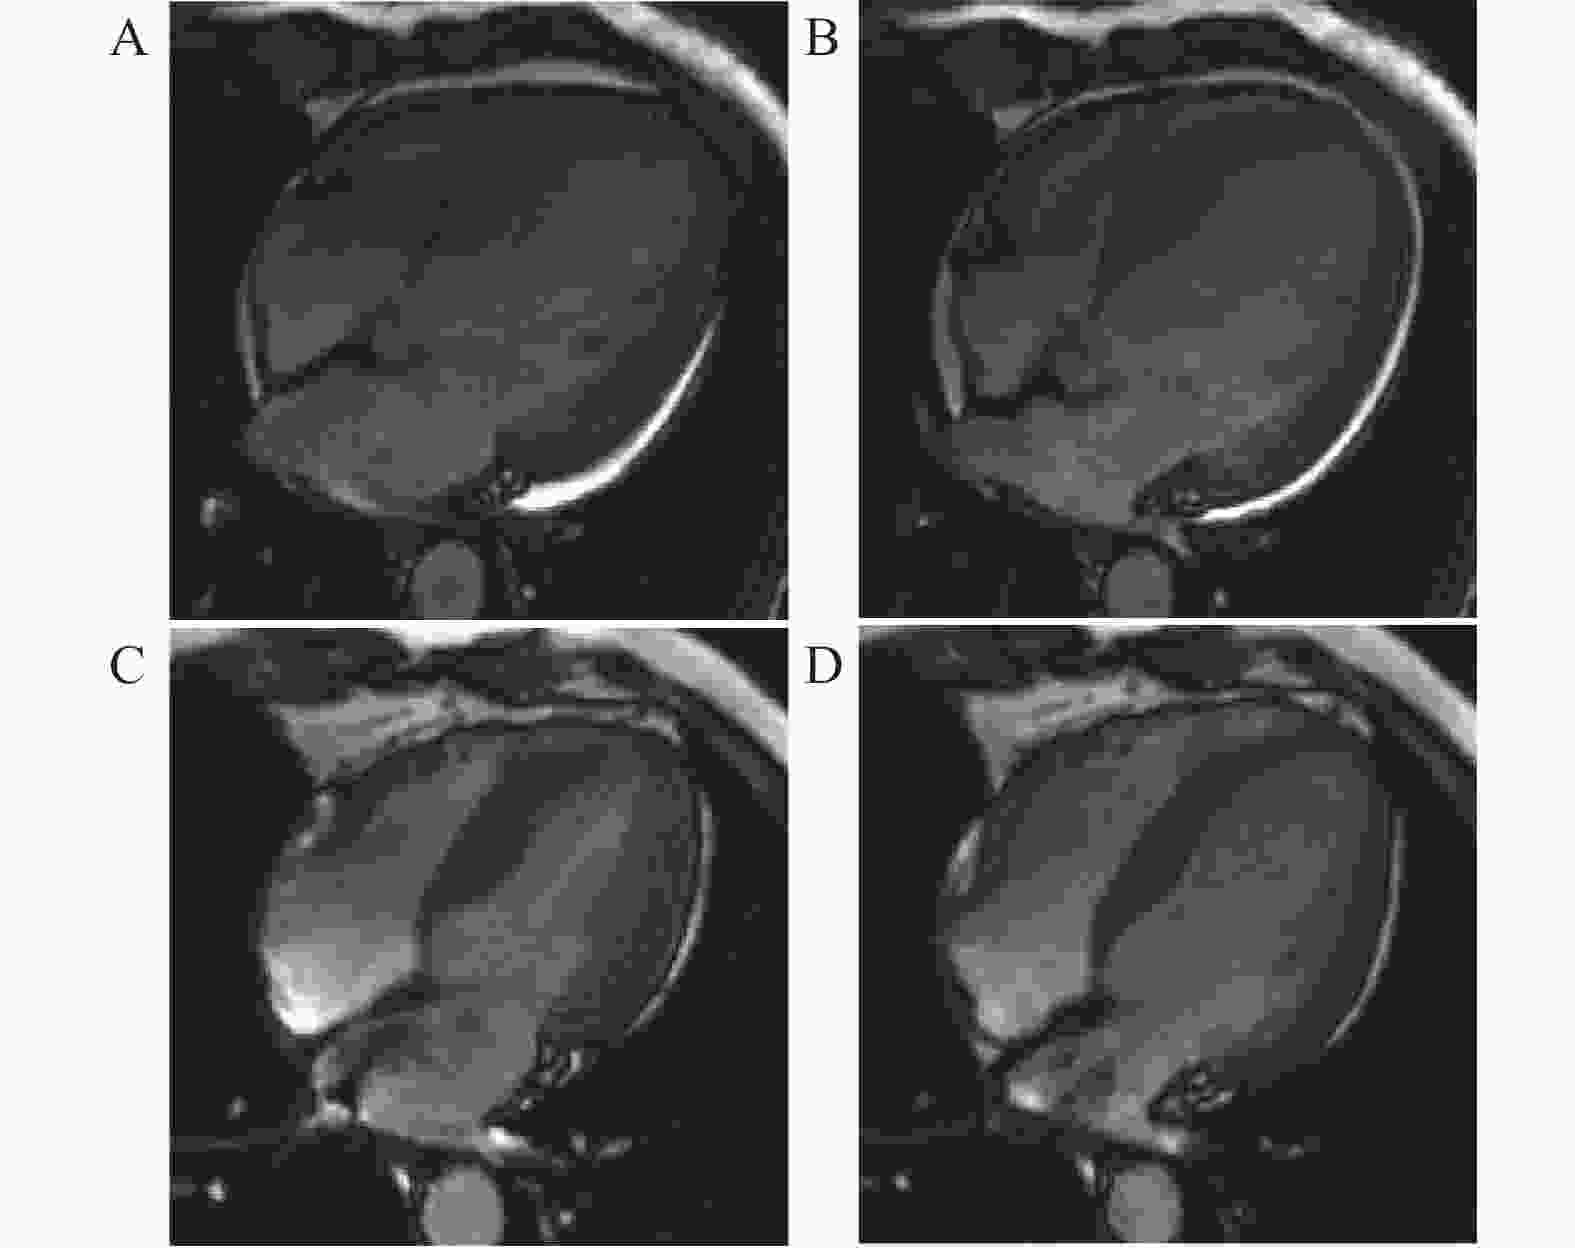

图  2  LVRR组CMR典型病例展示

A:治疗前四腔心电影序列收缩末期图像;B:治疗前四腔心电影序列舒张末期图像;C:治疗后四腔心电影序列收缩末期图像;D:治疗后四腔心电影序列舒张末期图像。

Figure  2.  LVRR Group CMR Typical Case Presentation